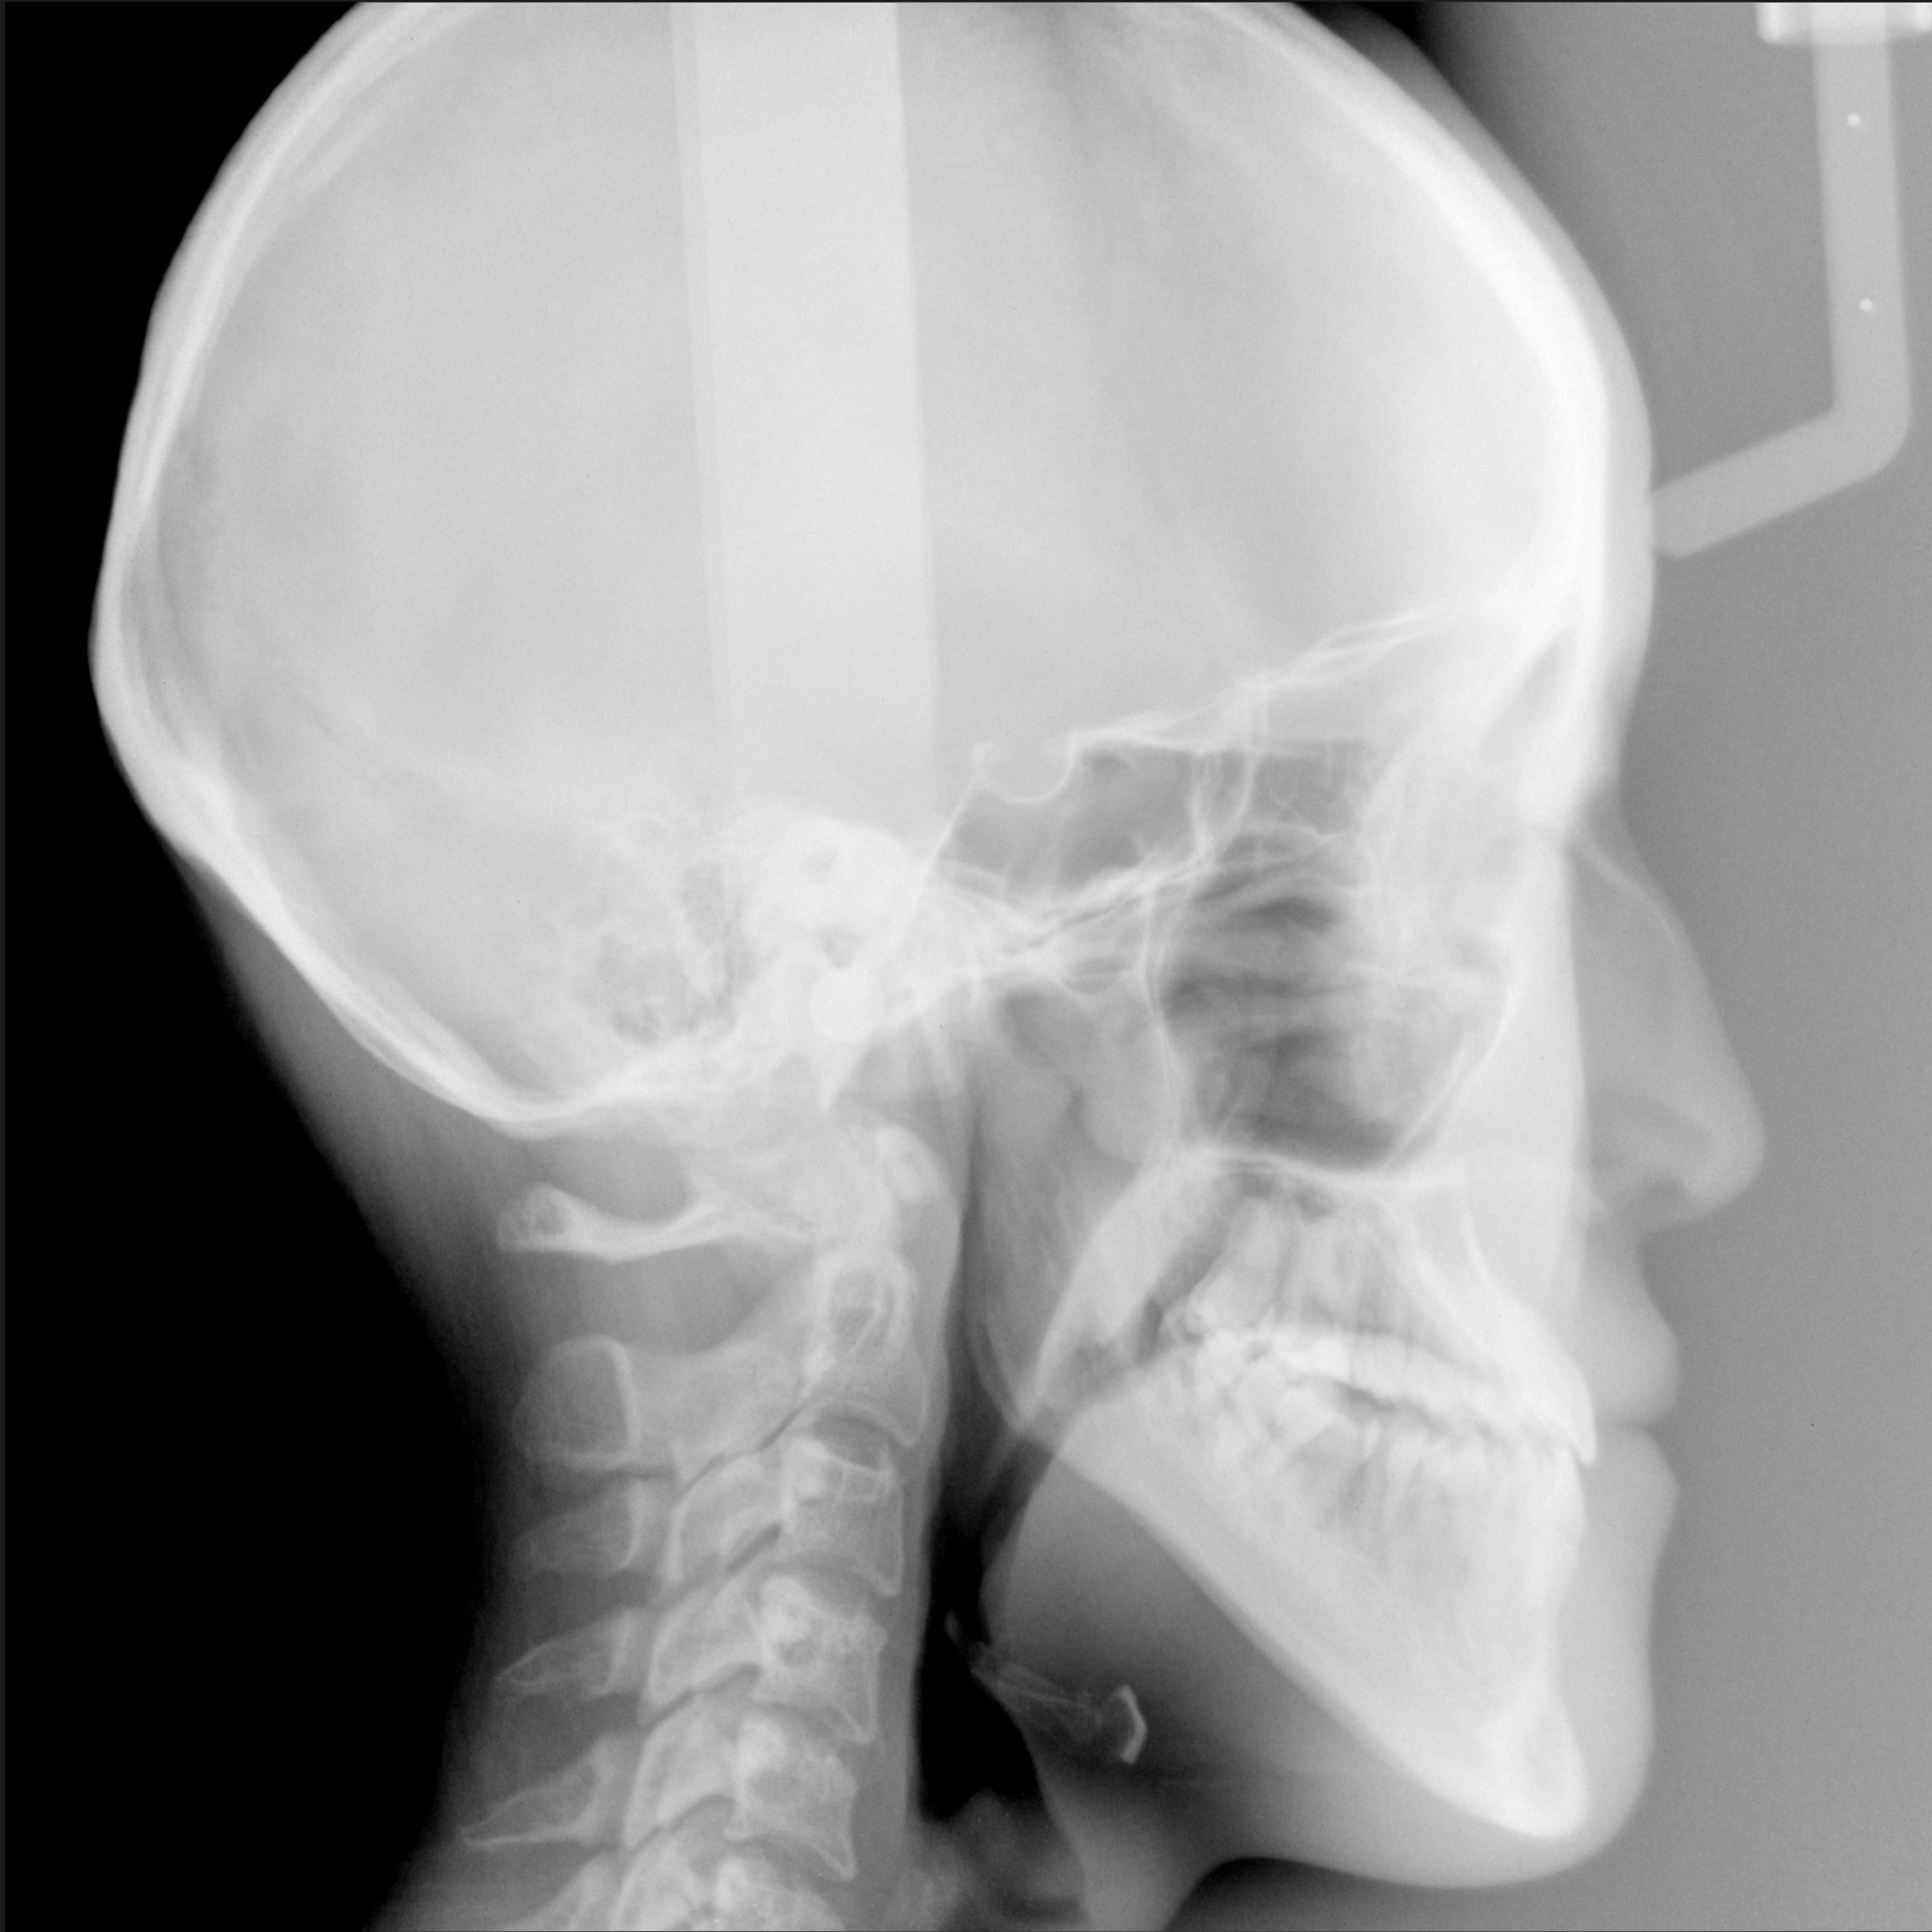

新着情報 0088治療後セファロ① – コピー Tweet 投稿日 : 2017年10月10日(火)カテゴリー : コメントを残す コメントをキャンセルメールアドレスが公開されることはありません。 * が付いている欄は必須項目ですコメント 名前 * メール * サイト 19歳 女性「手術をしないで 受け口を治したい」( 骨格的な反対咬合 ) ≫